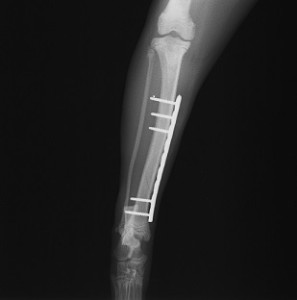

手術前 手術後

ロッキングプレートで整復しました。